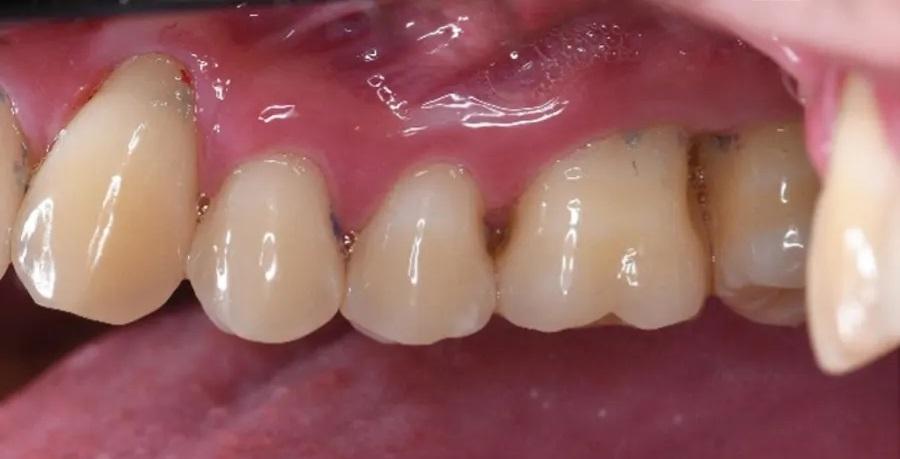

Фото 1 и Фото 2. Внеоральный осмотр выявил легкую болезненность в левом ВНЧС; интраоральный осмотр показал тонкий фенотип десны, локализованную рецессию десны и потерю клинического прикрепления. Предоперационные вестибулярный (Фото 1) и окклюзионный (Фото 2) виды показали воспаление десны, минимальную рецессию и глубину зондирования 12 мм с вестибулярной поверхности зуба № 2.6.